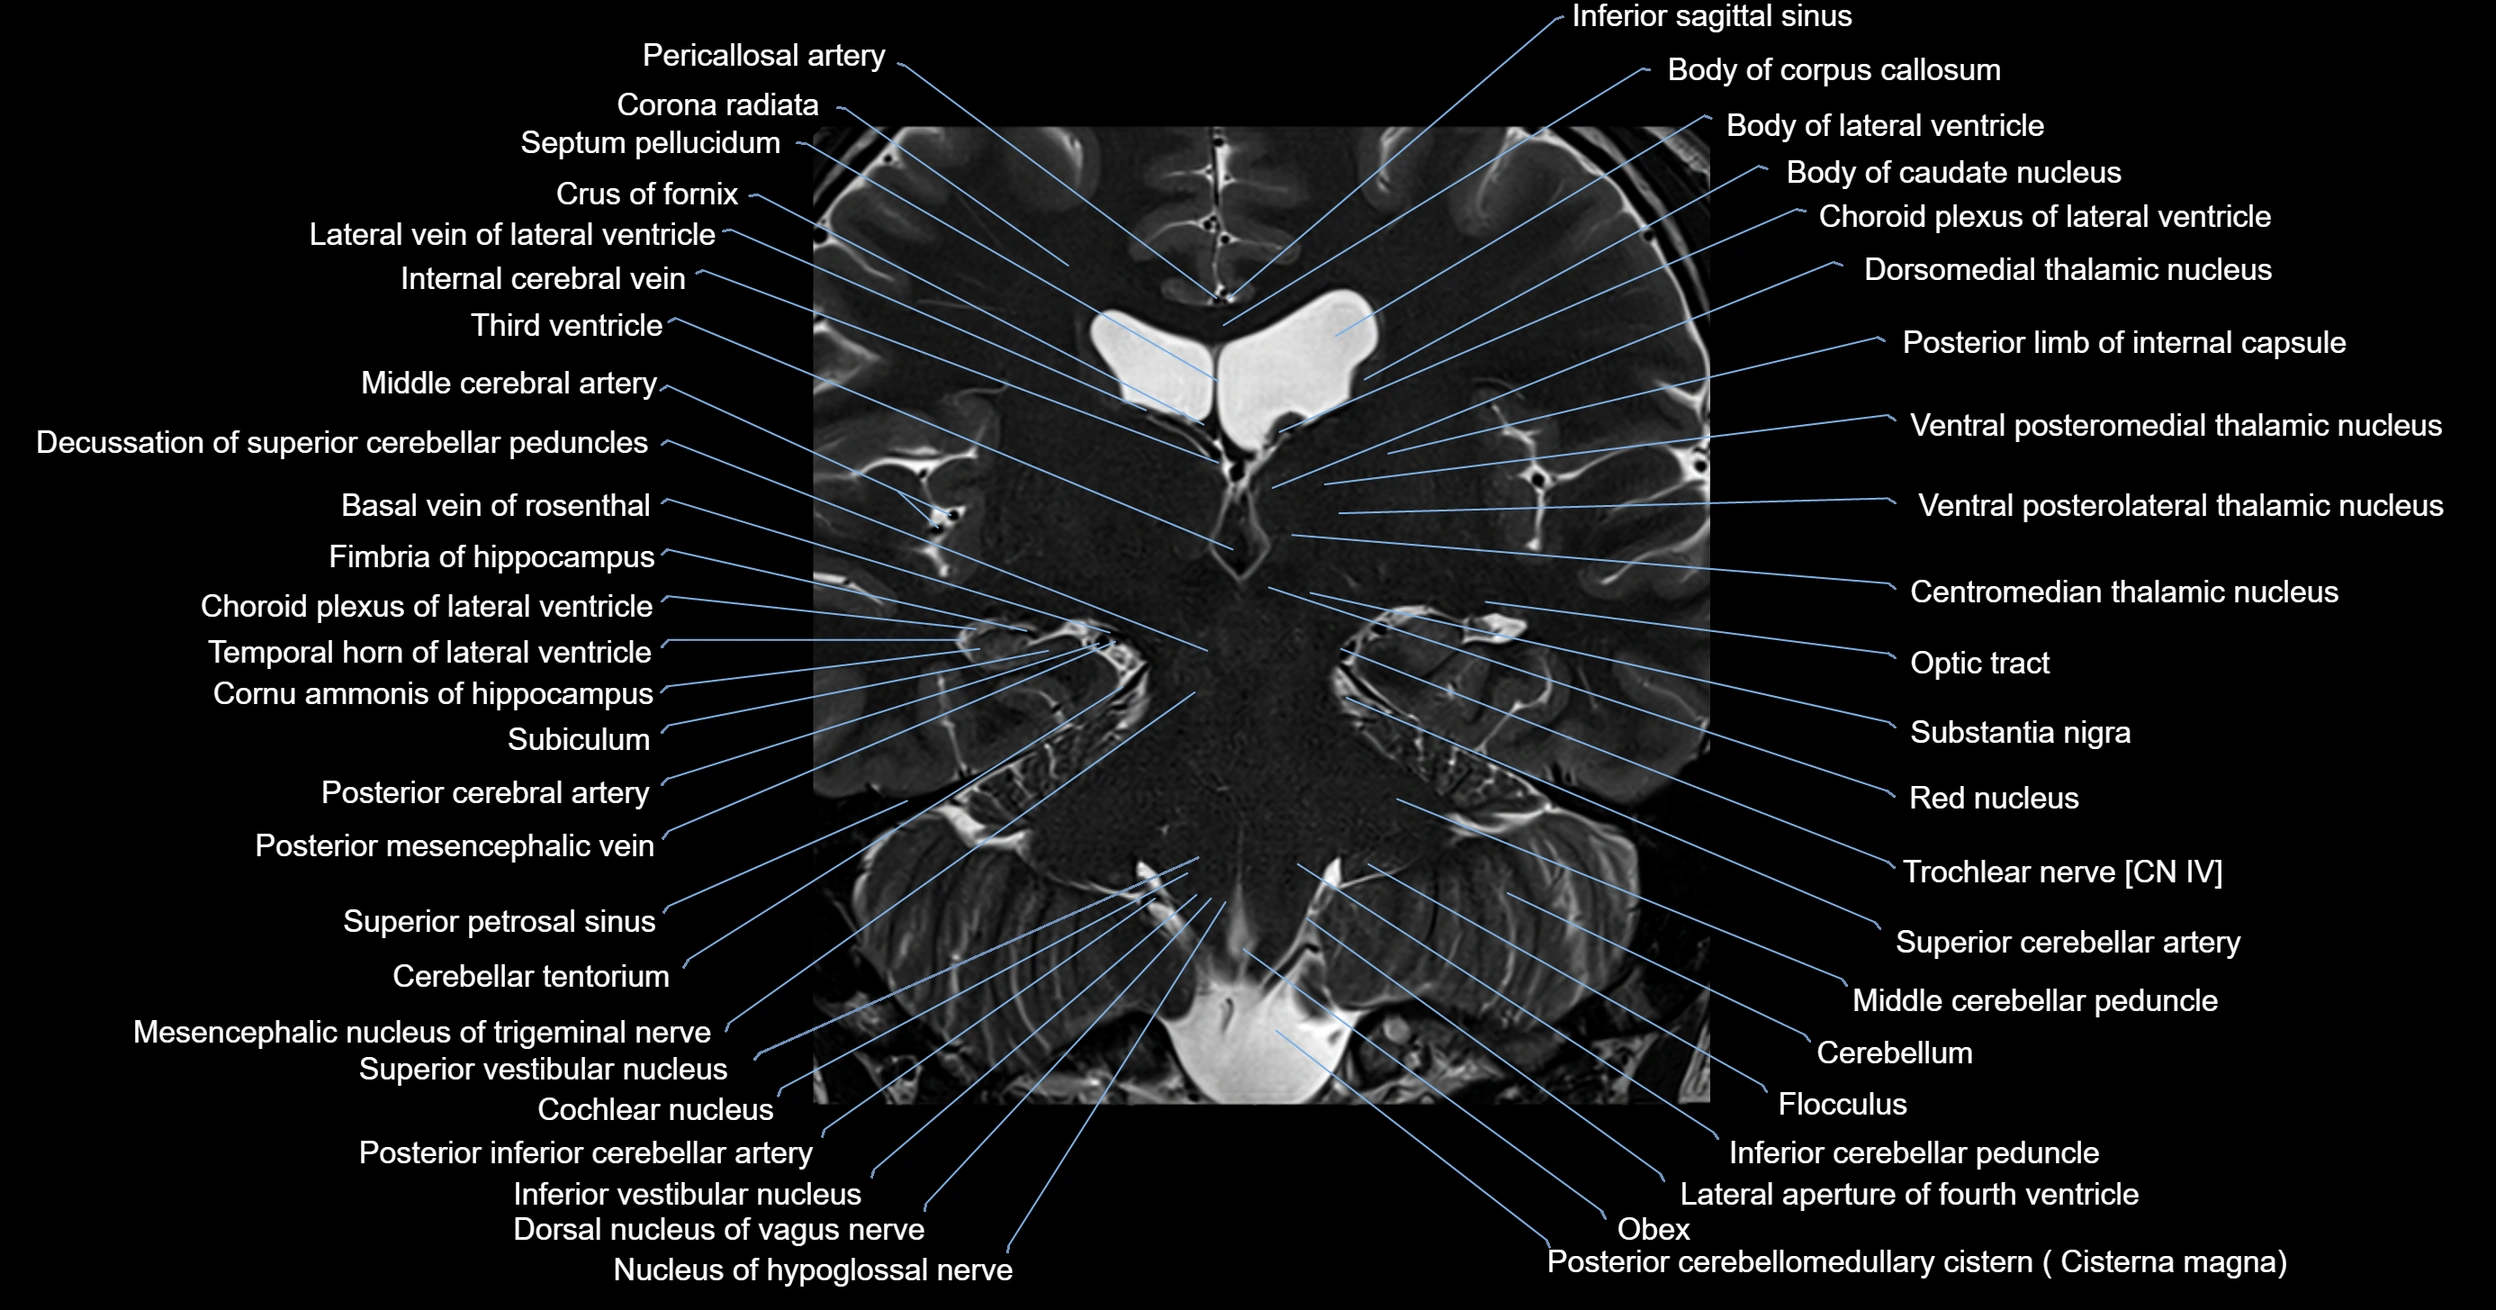

MRI images